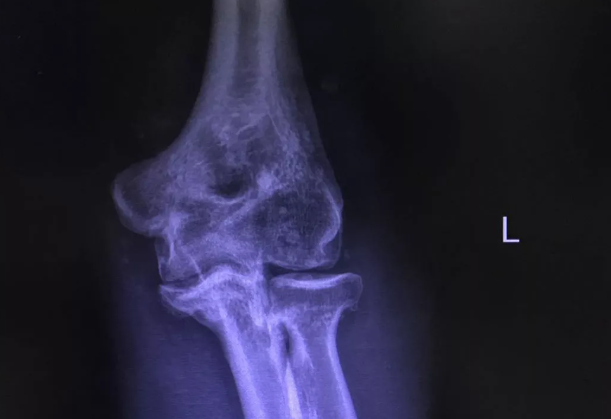

文章开头说到的袁伯伯,今年8月因左肘关节活动严重受限10年,加重伴疼痛一周前来就医,检查发现患上了滑膜软骨瘤病。

我院骨科就对袁伯伯开展了“关节镜下左肘关节探查+游离体摘除+病检术”。术后检查结果显示,可见关节处骨赘及游离体清除干净,袁伯伯肘关节屈伸活动得到明显改善,疼痛缓解,已康复出院。

术后左肘关节X光正位片